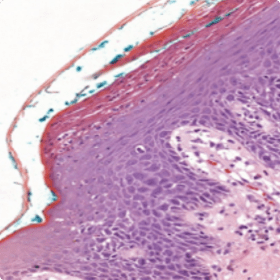

For more atypical presentations of psoriasis, a skin biopsy might be helpful10

An image of munro and kogoj micropustules

Munro and Kogoj micropustules

An image of vascular ectasia spongiform pustules

Vascular ectasia spongiform pustules

An image of prominent neutrophilic infiltrate

Prominent neutrophilic infiltrate